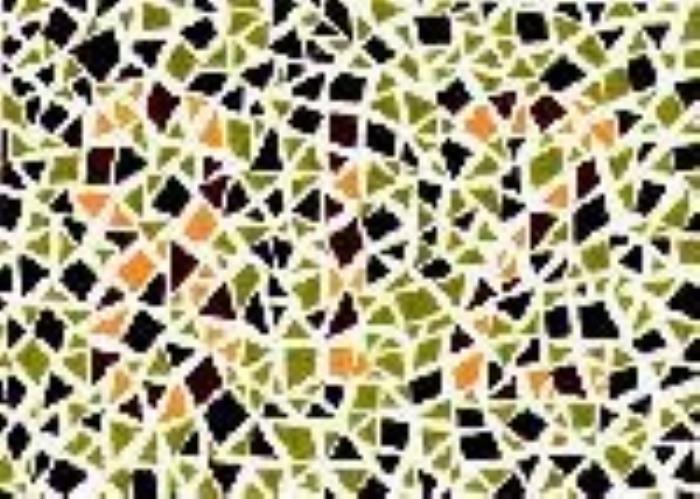

终极测试!!下面这张图你看到了什么数字?

结果:

左图:全色弱者及正常者读不出来,红绿色盲者及红绿色弱者大多能看到5

右图:正常者及全色弱者大多找不到,红绿色盲者及红绿色弱者容易找到

欢迎大家来评论一起猜一猜!